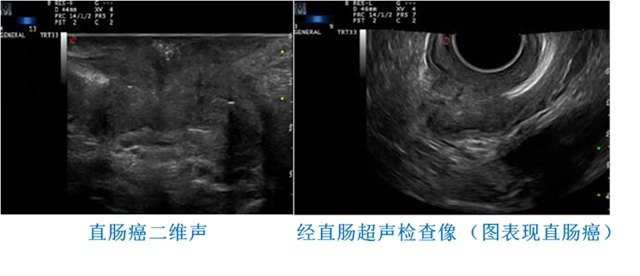

TRT33双平面腔内超声,穿透好、分辨率高,软组织层次结构显示清晰,可清楚显示肠周淋巴结、毗邻脏器和病变的关系,非常适合肛管检查及前列腺检查。

TRT33双平面腔内探头用于直肠检查优势:

1.        线阵扫查声束与肠壁和肌肉界面垂直,横断和纵切两组图像可综合分析病灶;

2.        13M探头对于组织细微结构显示分辨率高,彩色血流显示敏感度更佳;

3.        清楚地显示直肠壁各层次,对临床判定直肠癌的分期非常关键;

4.        操作简单,无创伤无辐射,动态实时显示,价格低廉。

TRT33双平面探头解决了临床其他检查存在的肠道高位肿瘤无法探及,病人较痛苦,可能产生出血、穿孔并发症,价格昂贵等不足。国内多个文献已报导,对于直肠癌的评价及判断周围组织侵犯程度确定癌肿分期,腔内超声的敏感性更高,可有效协助临床选择治疗方案。除此之外,对于肛周脓肿、肛瘘窦道定位、直肠肛门异物、对于外伤、产伤、手术伤等导致大便失禁者,双平面超声可显示括约肌损伤的程度及范围,对临床诊断、手术修补定位有明显的指导意义。